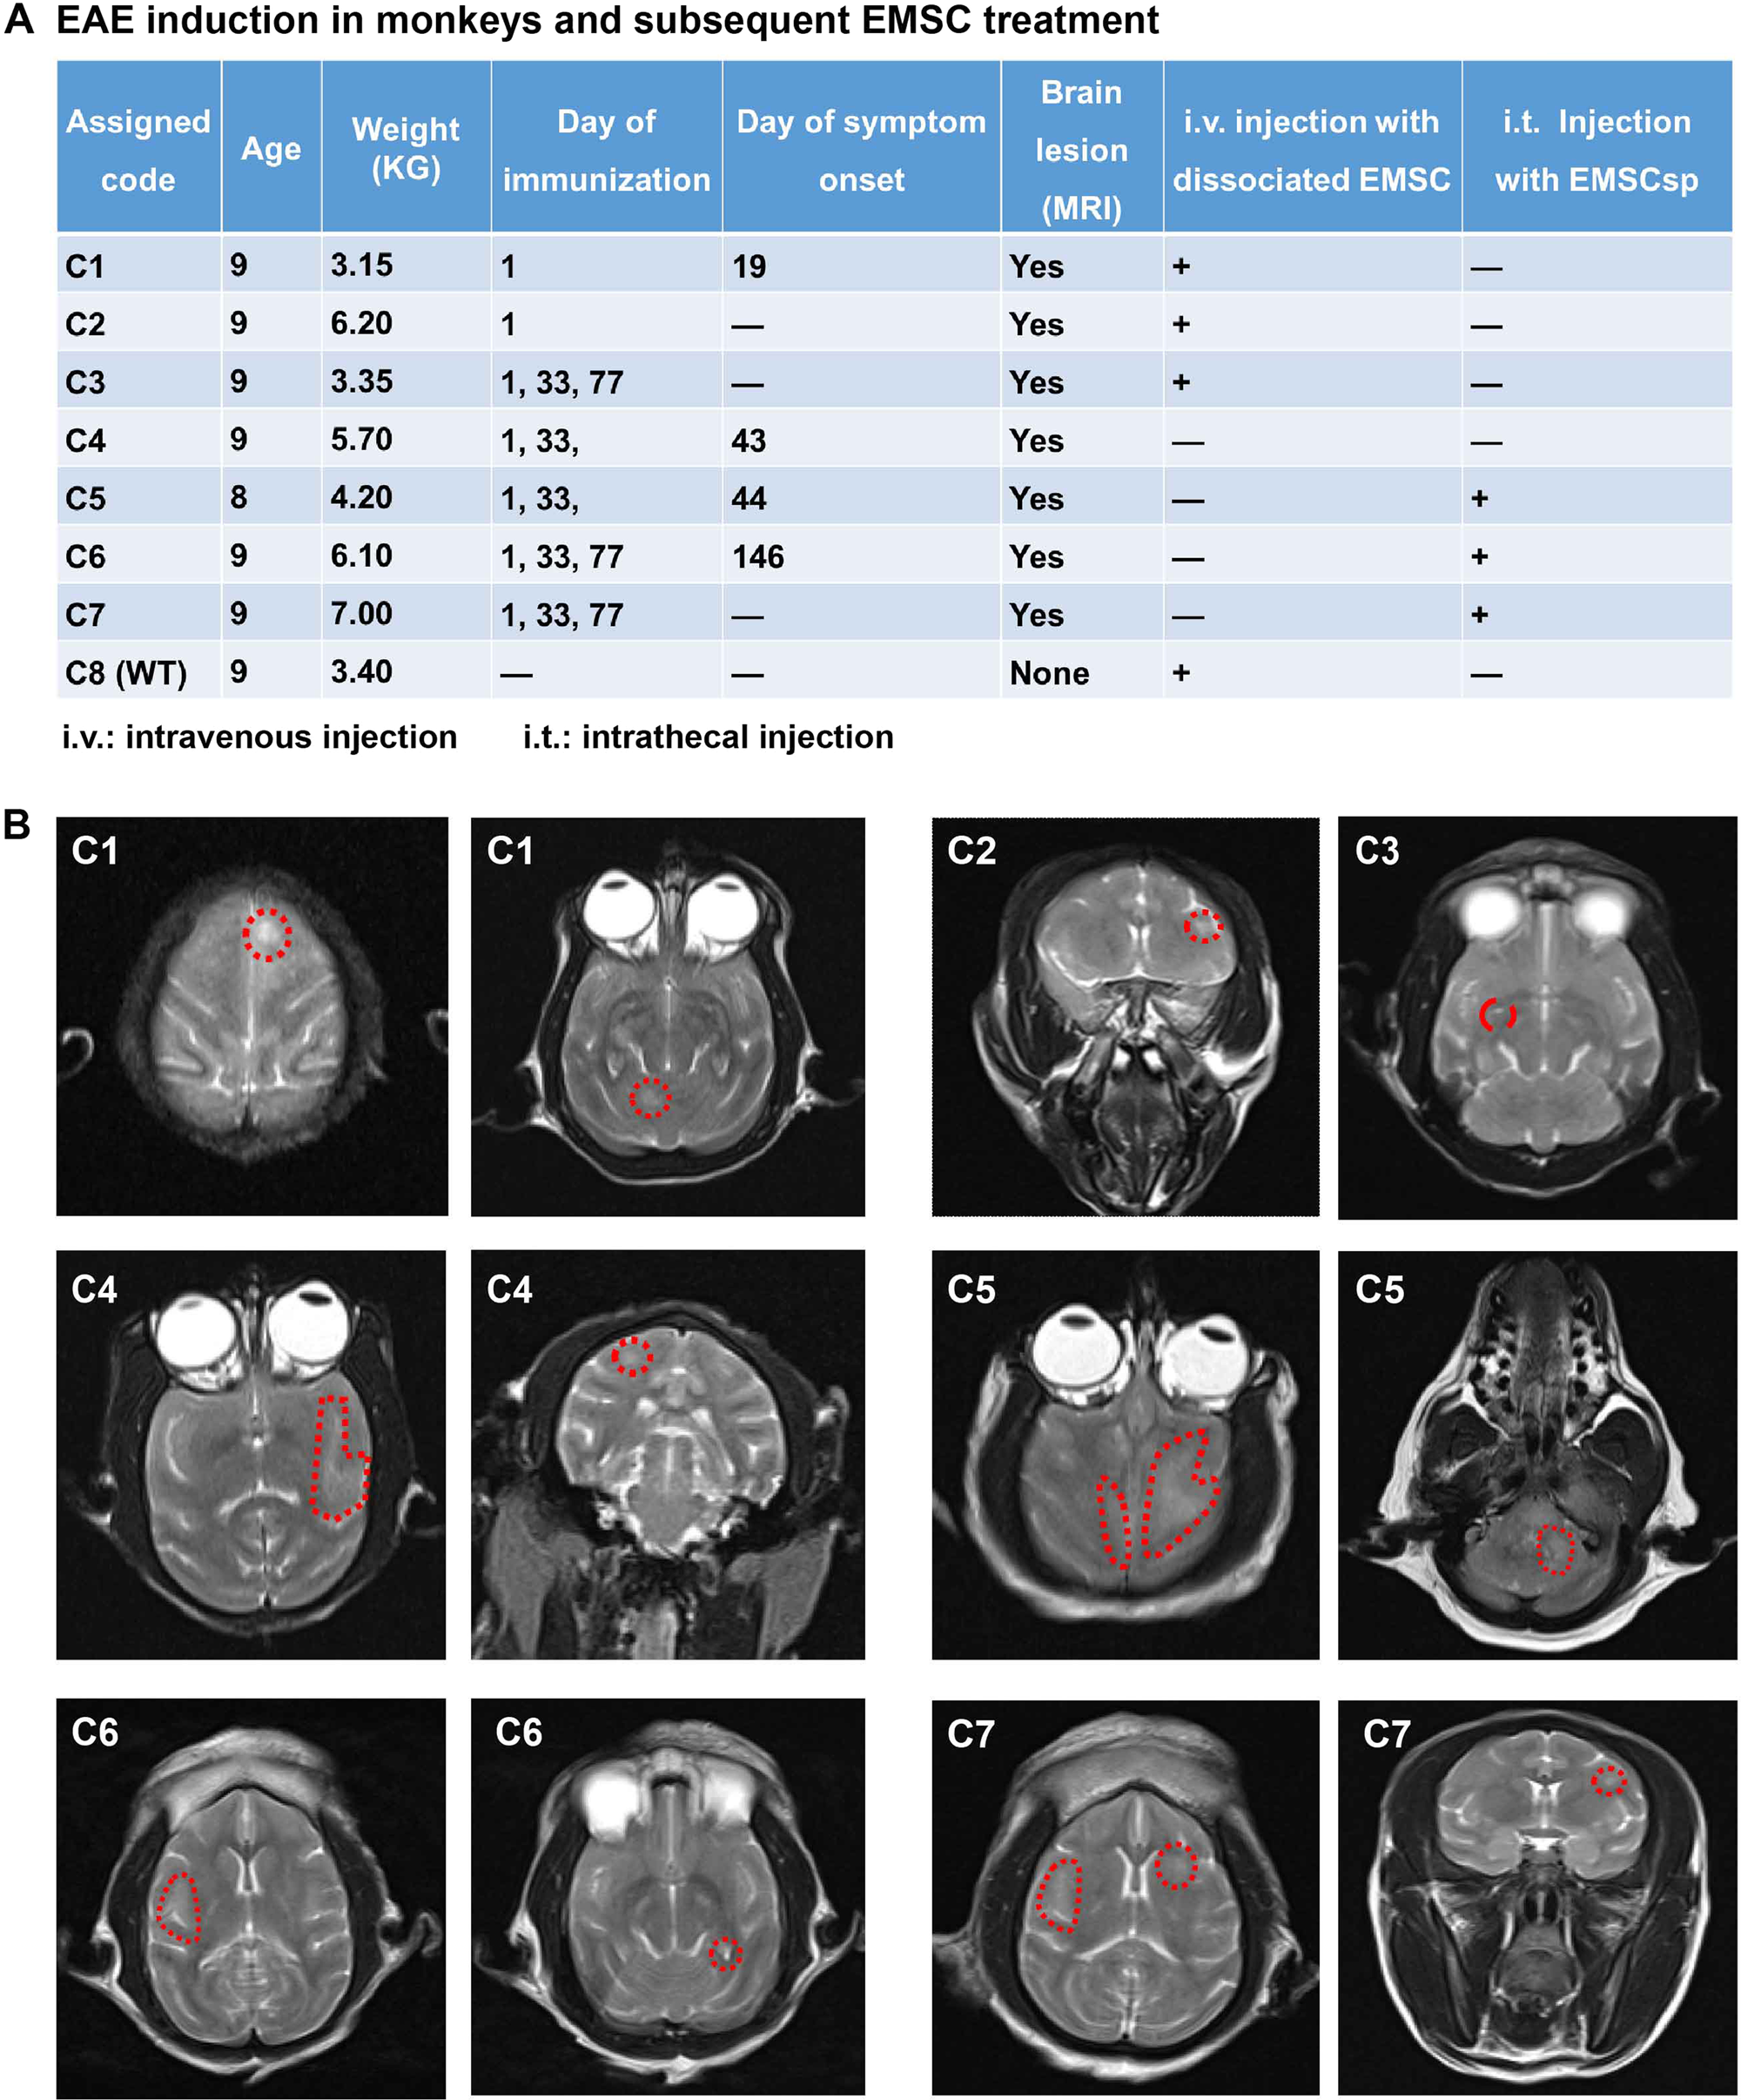

Fig. 1: EAE induction, EMSC treatment, and cerebral lesions in cynomolgus monkeys.

a EAE induction in monkeys and subsequent EMSC treatment. b MRI images of all the EAE-induced monkeys. Displayed are representative images of T2-weighted lesions marked with red dotted lines